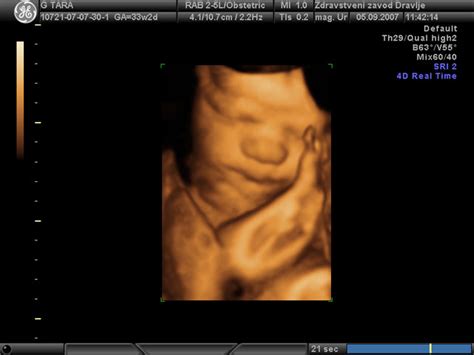

- 3D in 4D ultrazvok: Ti tehnologiji omogočata tridimenzionalne slike in gibanje v realnem času, kar staršem omogoča boljši vpogled v izgled otroka. Čeprav je njuna glavna prednost vizualizacija, lahko 3D ultrazvok pomaga pri merjenju volumnov in pridobivanju dodatnih ravninskih informacij.